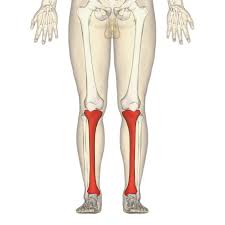

What is this region?

Tibia